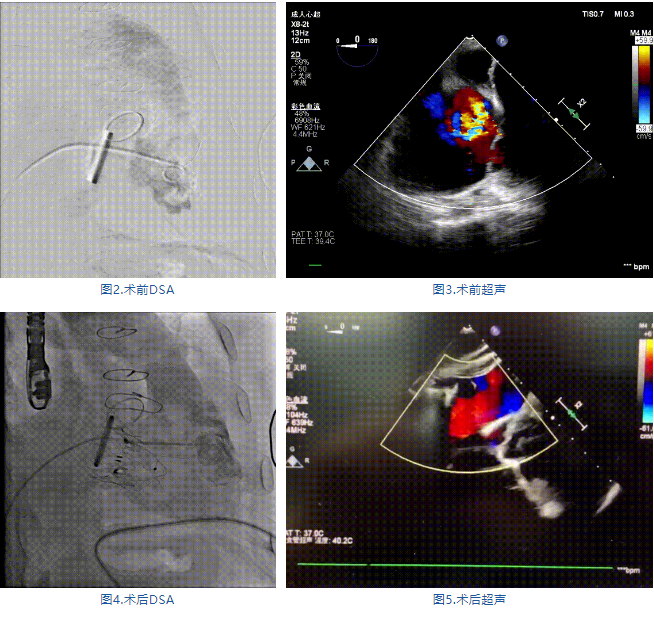

手術(shù)在全麻狀態(tài)下進(jìn)行,郭惠明教授團(tuán)隊(duì)采用經(jīng)右側(cè)頸靜脈入路的方式送入輸送器進(jìn)入體內(nèi),并在TEE和DSA的指引下進(jìn)行。在輸送器進(jìn)入右室后釋放室間隔錨定裝置,旋轉(zhuǎn)輸送器,使得錨定裝置對(duì)準(zhǔn)室間隔面;而后釋放前瓣夾持件,確定夾持件位于右室側(cè)釋放LuX-Valve Plus人工瓣膜盤片,再使用DSA和超聲確認(rèn)盤片是否位于右房側(cè),同時(shí)調(diào)整瓣膜的同軸性。緊接著在DSA和超聲的監(jiān)視下調(diào)整室間隔錨定件貼合室間隔,釋放室間隔錨定裝置。再次確認(rèn)瓣膜的穩(wěn)定性和同軸性后,將輸送器撤出體內(nèi),最終完成LuX-Valve Plus人工瓣膜植入(圖2-5),手術(shù)獲得圓滿成功?;颊咴谑中g(shù)室即刻拔除氣管插管,術(shù)后超聲提示LuX-Valve Plus人工三尖瓣瓣膜同軸性良好,瓣架固定牢靠,無(wú)反流和瓣周漏。